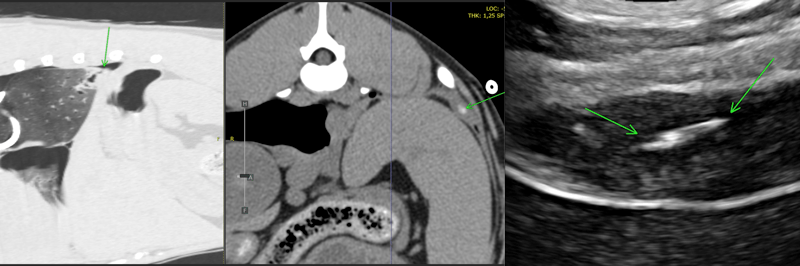

Figure 2